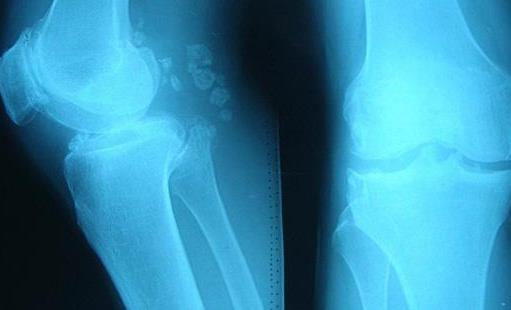

2、膝关节

膝关节在人体的众多关节之中,承受的压力是很大的,毕竟人体的自重都会积压到这个关节之上,因此膝关节出现病变的几率也是最高的,尤其是骨刺这种疾病。而对于膝关节有骨刺的患者来说,基本都会出现跛行和关节肿胀性疼痛的症状,当做体力劳动之时,这种症状会更加的明显。